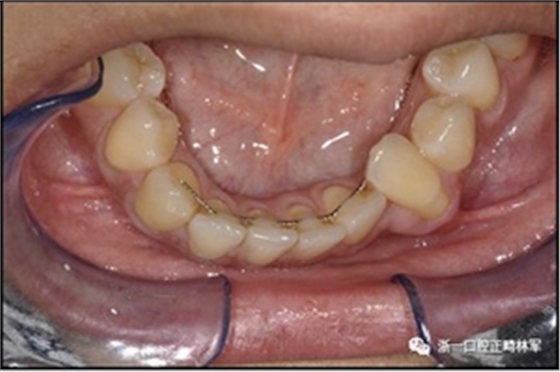

臨床檢查顯示固定保持器完好,弓絲沒(méi)有斷裂(圖13)。在下頜右側(cè)中切牙唇側(cè)和鄰近側(cè)切牙的舌側(cè)注意到有牙齦退縮。這些牙齒在退縮方向上存在顯著的扭矩差異。下頜的左側(cè)尖牙頰側(cè)錯(cuò)位,而右側(cè)尖牙舌側(cè)傾斜。三維射線照片證實(shí)了下頜右側(cè)尖牙面?zhèn)妊啦酃菃适?,右?cè)中切牙的喪失程度較輕。右側(cè)側(cè)切牙根也從舌側(cè)骨面上扭轉(zhuǎn)出來(lái)(圖14)。

圖13.粘合到尖牙和切牙上的柔性螺旋弓絲保持器,伴有牙齦退縮和附著喪失,中切牙之間嚴(yán)重的扭矩差異以及兩顆尖牙的橫向移動(dòng)和扭矩。牙周問(wèn)題和牙齒移動(dòng)的嚴(yán)重程度均為牙周正畸聯(lián)合治療的指征:A,正面視圖; B,咬合面視圖。